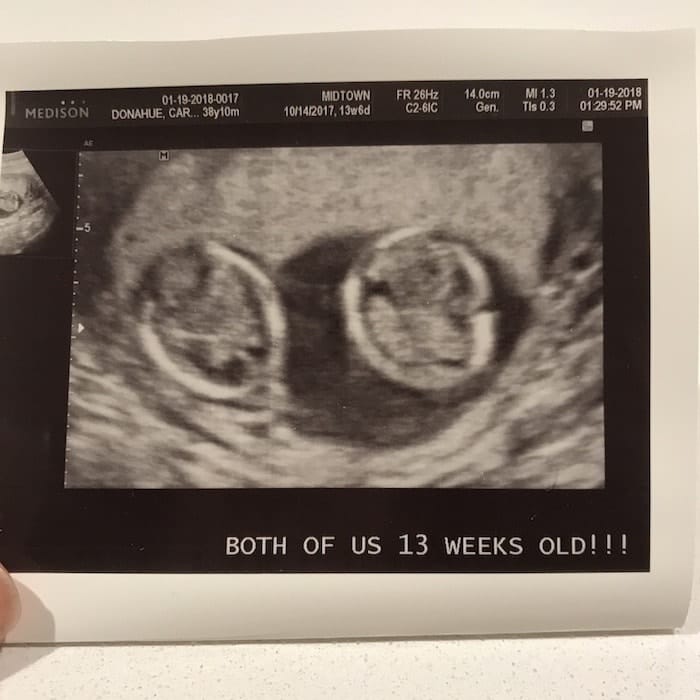

- Ultrasound Photos at 13 Weeks Pregnant With Twin

Ultrasound Photos at 13 Weeks Pregnant With Twin